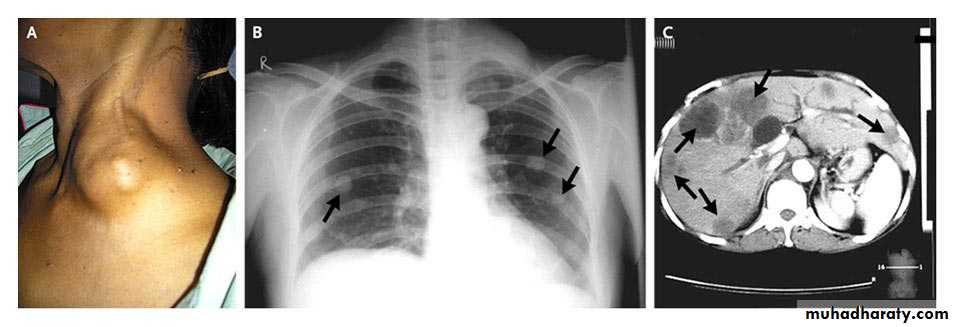

Loh K and Yushak A. N Engl J Med 2007;357:282

A 56-year-old woman presented with jaundice and a painless mass in her left supraclavicular fossa that had become progressively enlarged during the preceding 8 weeks

Clinical images